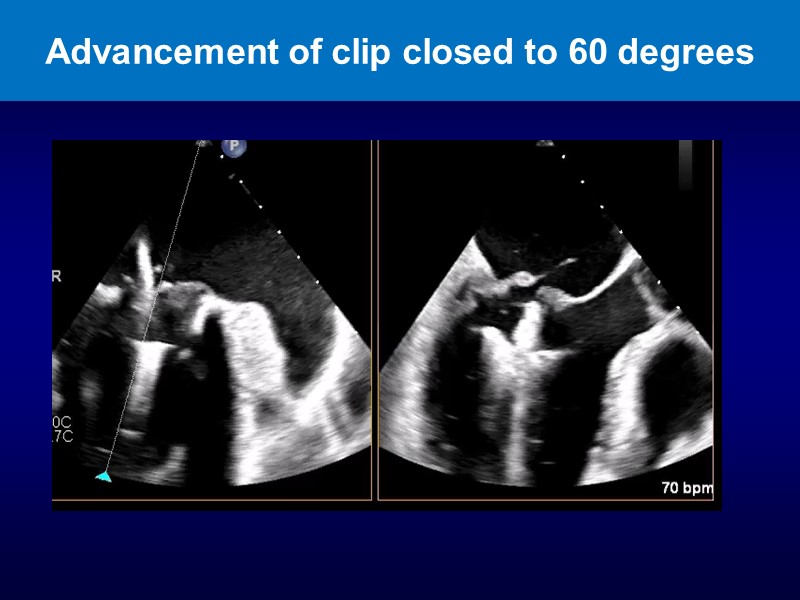

- To get up to date on MitraClip therapy's recent clinical evidences and innovation